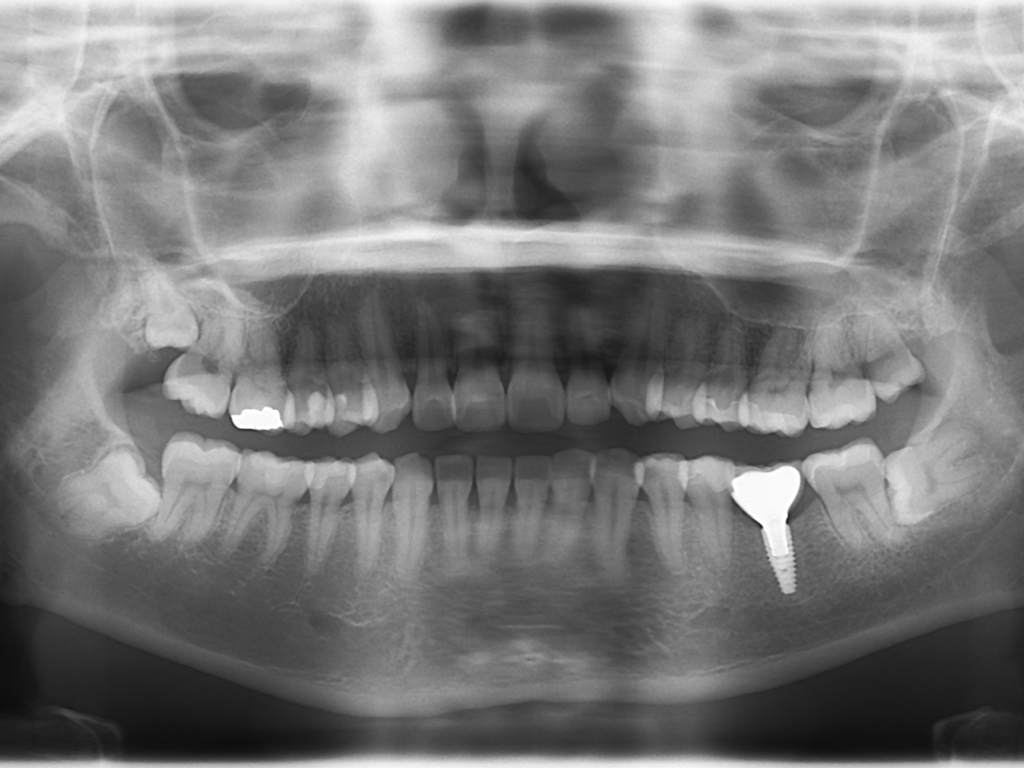

[レントゲン術後]

[レントゲン術後]